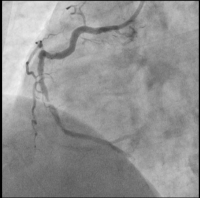

RCA

Abbildung 1: RCA: proximal wirksam und im mittleren Hauptstamm hochgradig stenosiert (schuldige Läsion)